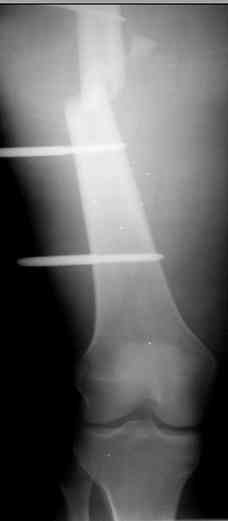

Коллеги! Прошу совета, какую тактику избрать при лечении.Больной 27 лет, мотоциклист. Поступил 23.04.10 ДЗ. О. перелом н.з левого бедра Gustillo 3b (c повреждение бедренной вены), О.Правого бедра Gustillo 2, з. фрагментарный перелом левой голени.При поступлении Hb 66 ISS 40, Фиксация стержневыми аппратами, сосудистые хирурги выполнили шов вены. Выполена резекция бедренной кости 9 см. На 7 сутки Желудочно-кмшечное кроветечение из стрессовых язв, 12 сутки флотирующий тромтоз 14 см установлен кава-фильтр. На 15 сутки закрытие ран местными тканями. Раны заживают первично. Воспаления на стержнях нет. В настоящий момент планируем. Переход со стержневых аппаратов на стержни с антибактериальным покрытием на правом бедре и левой голени. Левое бедро планируем продолжить фиксировать в стержневом аппарате.

Вопрос: что делать с левым бедром? Учитывая внутрисутавной характер перелома, дефект бедра 9 см.

Вчера перешли с аппаратов на стежни с аб покрытием на правом бедре и левой голени.

На левом бедре оставили аппарат бедро-голень.